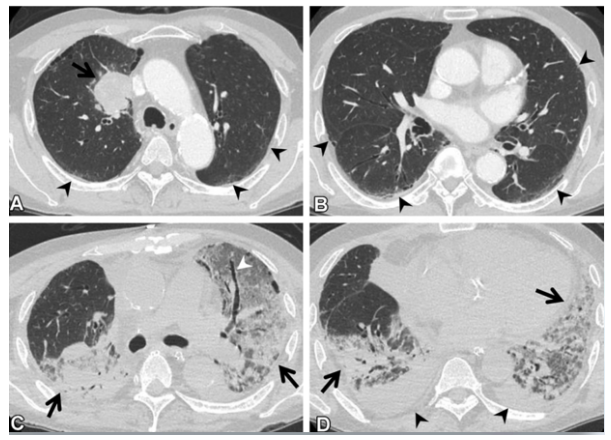

(1)感染性疾病:病毒性?细菌性?真菌?非典型病原体?吸入性肺炎?(2)非感染性疾病:心衰?急性肺栓塞?自身免疫性疾病?麻醉/手术相关肺损伤?急性间质性肺炎?回顾分析患者入院时胸部CT: 双肺靠近外周近胸膜处有轻微细小间质样改变(图4)。诊断:急性间质性肺炎;Ⅰ型呼吸衰竭;左肺下叶部分切除术后;高血压病。ECMO支持;呼吸机支持;甲泼尼松80 mg q12h,尼达尼布;镇静镇痛;抗感染;营养支持。ECMO第6天, 术后第18天, 肺部病变进一步加重(图5)。血气分析: pH 7.543, PaO2 154 mmHg, PaCO2 33.2 mmHg(ECMO, FiO2 100%, MV FiO2 60%)。术后第26天复查胸部CT未见改善。患者最终死亡。笔者团队也曾接诊过一例早期肺癌患者,2013年和2014年随访肺部结节均无明显变化。2015年胸部手术后2天,两肺变白(图6)。当时医生警惕性非常高,立刻行胸部CT检查并予相应治疗,患者最终存活。2022年RadioGraphics 杂志报道一例85岁女性腺癌患者奥希替尼治疗5个月后。图7-A和B为治疗前胸部CT图像,可见右肺中叶有肿块(A中箭头)。胸膜下区域磨玻璃改变和网状结构(箭头)提示存在间质性肺异常(Interstitial Lung Abnormalities,ILA)。治疗5个月后的轴位CT图像显示肿块(C中白色箭头)、弥漫性磨玻璃改变和合并症(黑色箭头)。图源:Radiographics, 2022, 42(7):1925-1939.另一例66岁右上肺鳞癌患者,术前CT显示肿块(图8-A中箭头)位于肺右上叶。轻度磨玻璃改变(箭头),提示ILA,见于胸膜下区域。图8-C和D为术后CT,显示弥漫性磨玻璃样改变和实变(箭头),牵引性支气管扩张症(图8-C中箭头),也可见胸腔积液(图8-D中箭头)。图源:Radiographics, 2022, 42(7):1925-1939.